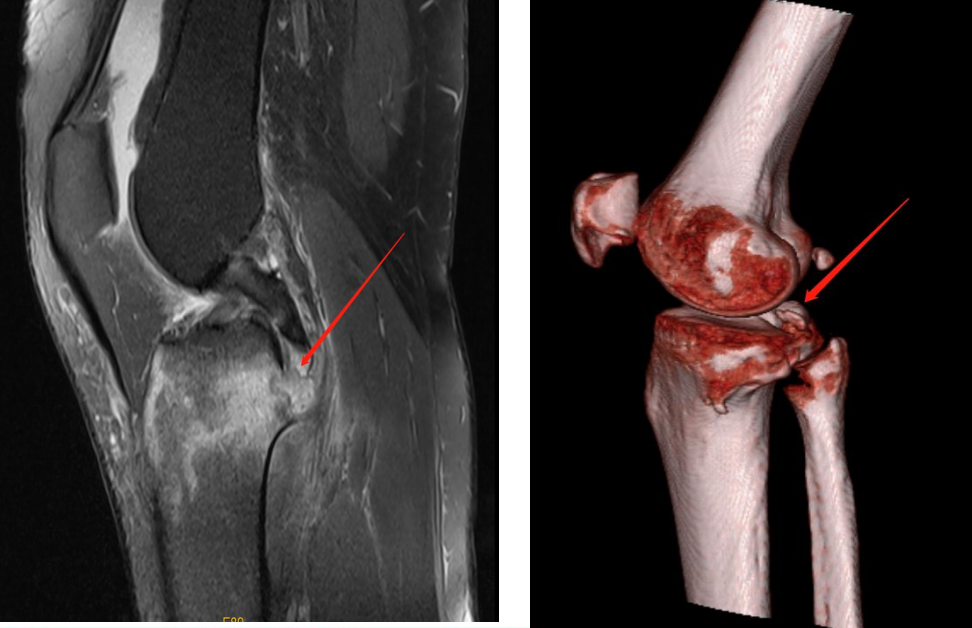

后交叉韧带止点撕脱骨块

3D Model Demonstration

分型及术式

ⅢB型:多块撕脱骨折;合并半月板撕裂;BC>15mm;AE/AD≥1/2。

术式: 双袢(后叉前建立骨道)+骨道固定

合并内侧半月板放射裂

撕脱骨折、内侧半月板放射裂

半月板骨道固定、双袢固定撕脱骨折

术后X线片